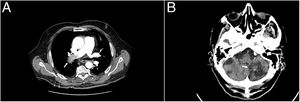

Complementary tests determined partial respiratory failure with a pO2 of 51mmHg, the glucose of 186mg/dl, a troponin T hs of 17.74pg/ml (0.00–14), and a d-dimer of 20,000ng/ml (0.10–500), during hospitalisation for PICA stroke it was 2200.00. Arterial blood PaCO2, creatinine levels, coagulation study, and EKC record were in normal range. A computed tomography chest angiography (CTA chest) revealed a filling defect in right main artery with extension to all lobar branches and most of its segmental, contralateral segmental arteries of the left lobe and superior lobar artery with extension to lingula, an increase in the calibre of the pulmonary artery and a mild rectification of the interventricular septum (Fig. 1, Image A). Transthoracic echocardiogram (TTE) performed one day after admission showed moderate pulmonary hypertension without signs of ventricular dysfunction, and Doppler ultrasonography in lower extremities demonstrated thrombus in right popliteal vein. The diagnosis of intermediate-high risk acute pulmonary embolism, PESI 105, class III, was made

Given the background of stroke with haemorrhagic transformation and the bleeding risk (RIETE bleeding score 3, intermediate risk), we decided to use prophylactic enoxaparin doses (40mg/24h), and placed a temporary vena cava filter on the second day of admission. Ten days after admission, we repeated the brain computed tomography scan, without signs of rebleeding three weeks after the haemorrhagic transformation (Fig. 1, Image B), so we decided to start apixaban 2.5mg/12h. Admission was maintained four more days for evolutionary surveillance, and since no new neurological symptoms were present, he was discharged and followed up in consultation two weeks later. We removed the vena cava filter on scheduled intervention one week after the start of the anticoagulation therapy.